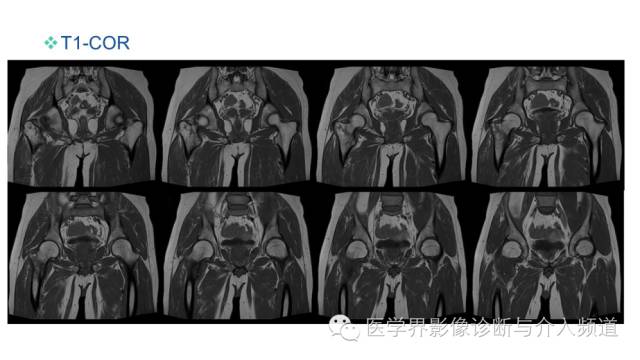

MR平扫及增强示:

右侧股骨上段见不规则形长T1短等T2异常信号,直径约1.5cm,邻近骨皮质破坏,其内骨髓可见斑片状长T1等长T2混杂信号,边界不清,股前方可见软组织肿块,呈长T1等长T2混杂信号,DWI呈明显高信号;注入GD-DTPA后,股骨内病灶呈轻度强化,周围软组织呈明显不均质强化。左侧髋关节诸组成骨对位关系可,未见明显骨质破坏征象,双侧髋关节可见少量斑片状长T2液体信号影。